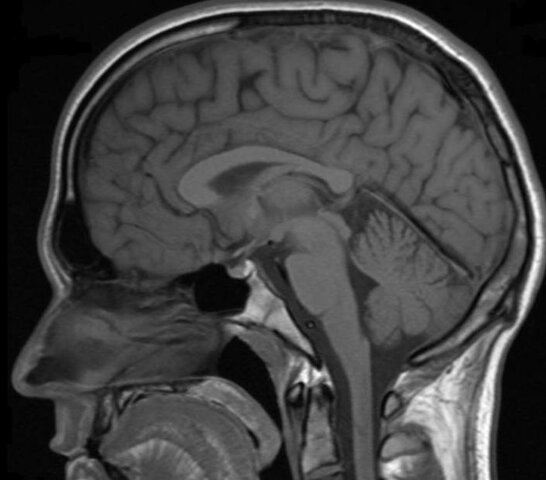

Paul Lauterbur (1929-2007) y Peter Mansfield (1933) recibieron el premio Nobel de Medicina por sus descubrimientos sobre la Resonancia Magnética.